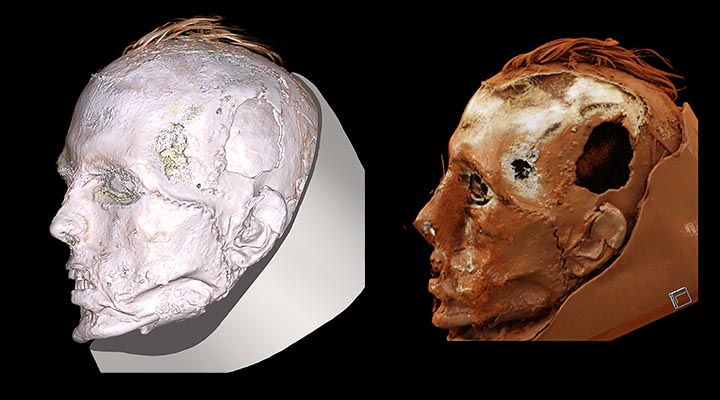

He was from the mountainous region of modern-day Khakasia, aged 25 to 30 when he died 1,700 years ago. Another CT scan showed the face of his gypsum death mask that was all the rage with the ancient Tashtyk people, who were settled cattle-breeders and farmers known for their idiosyncratic burial rituals.

Dr Pankova said the mask ‘has black stripes on a red background, plus the lower part of the mask was somewhat destroyed and man’s teeth can be seen.

‘So all together it creates such an aggressive look.’ Yet under the mask ‘there was nothing aggressive in this face.

‘It was the face of a calmly sleeping person.

‘The mask was very close in appearance to the real face.

‘For the first time we see the real face of a young man of this time.

‘The computer scan allowed us to see, so to say, three layers – the layer of the mask, the layer of the face without the mask and layer of the skull.’ The face of the woman lying in the same burial chamber – also buried in a fur coat – has not been revealed with a CT scan.